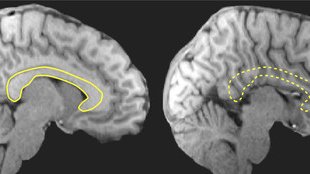

The Effects of Brain Defects

Tenzin Yin, a University of Florida senior double majoring in philosophy and interdisciplinary computational neuroscience, is researching brain activity in people with a birth defect called agenesis of the corpus callosum. The corpus callosum is a structure that connects the two hemispheres of the human brain.

Through the Amgen Scholars program, she is working in the lab of Ralph Adolphs, (PhD '92), Bren Professor of Psychology, Neuroscience, and Biology; Allen V. C. Davis and Lenabelle Davis Leadership Chair and director of the Caltech Brain Imaging Center